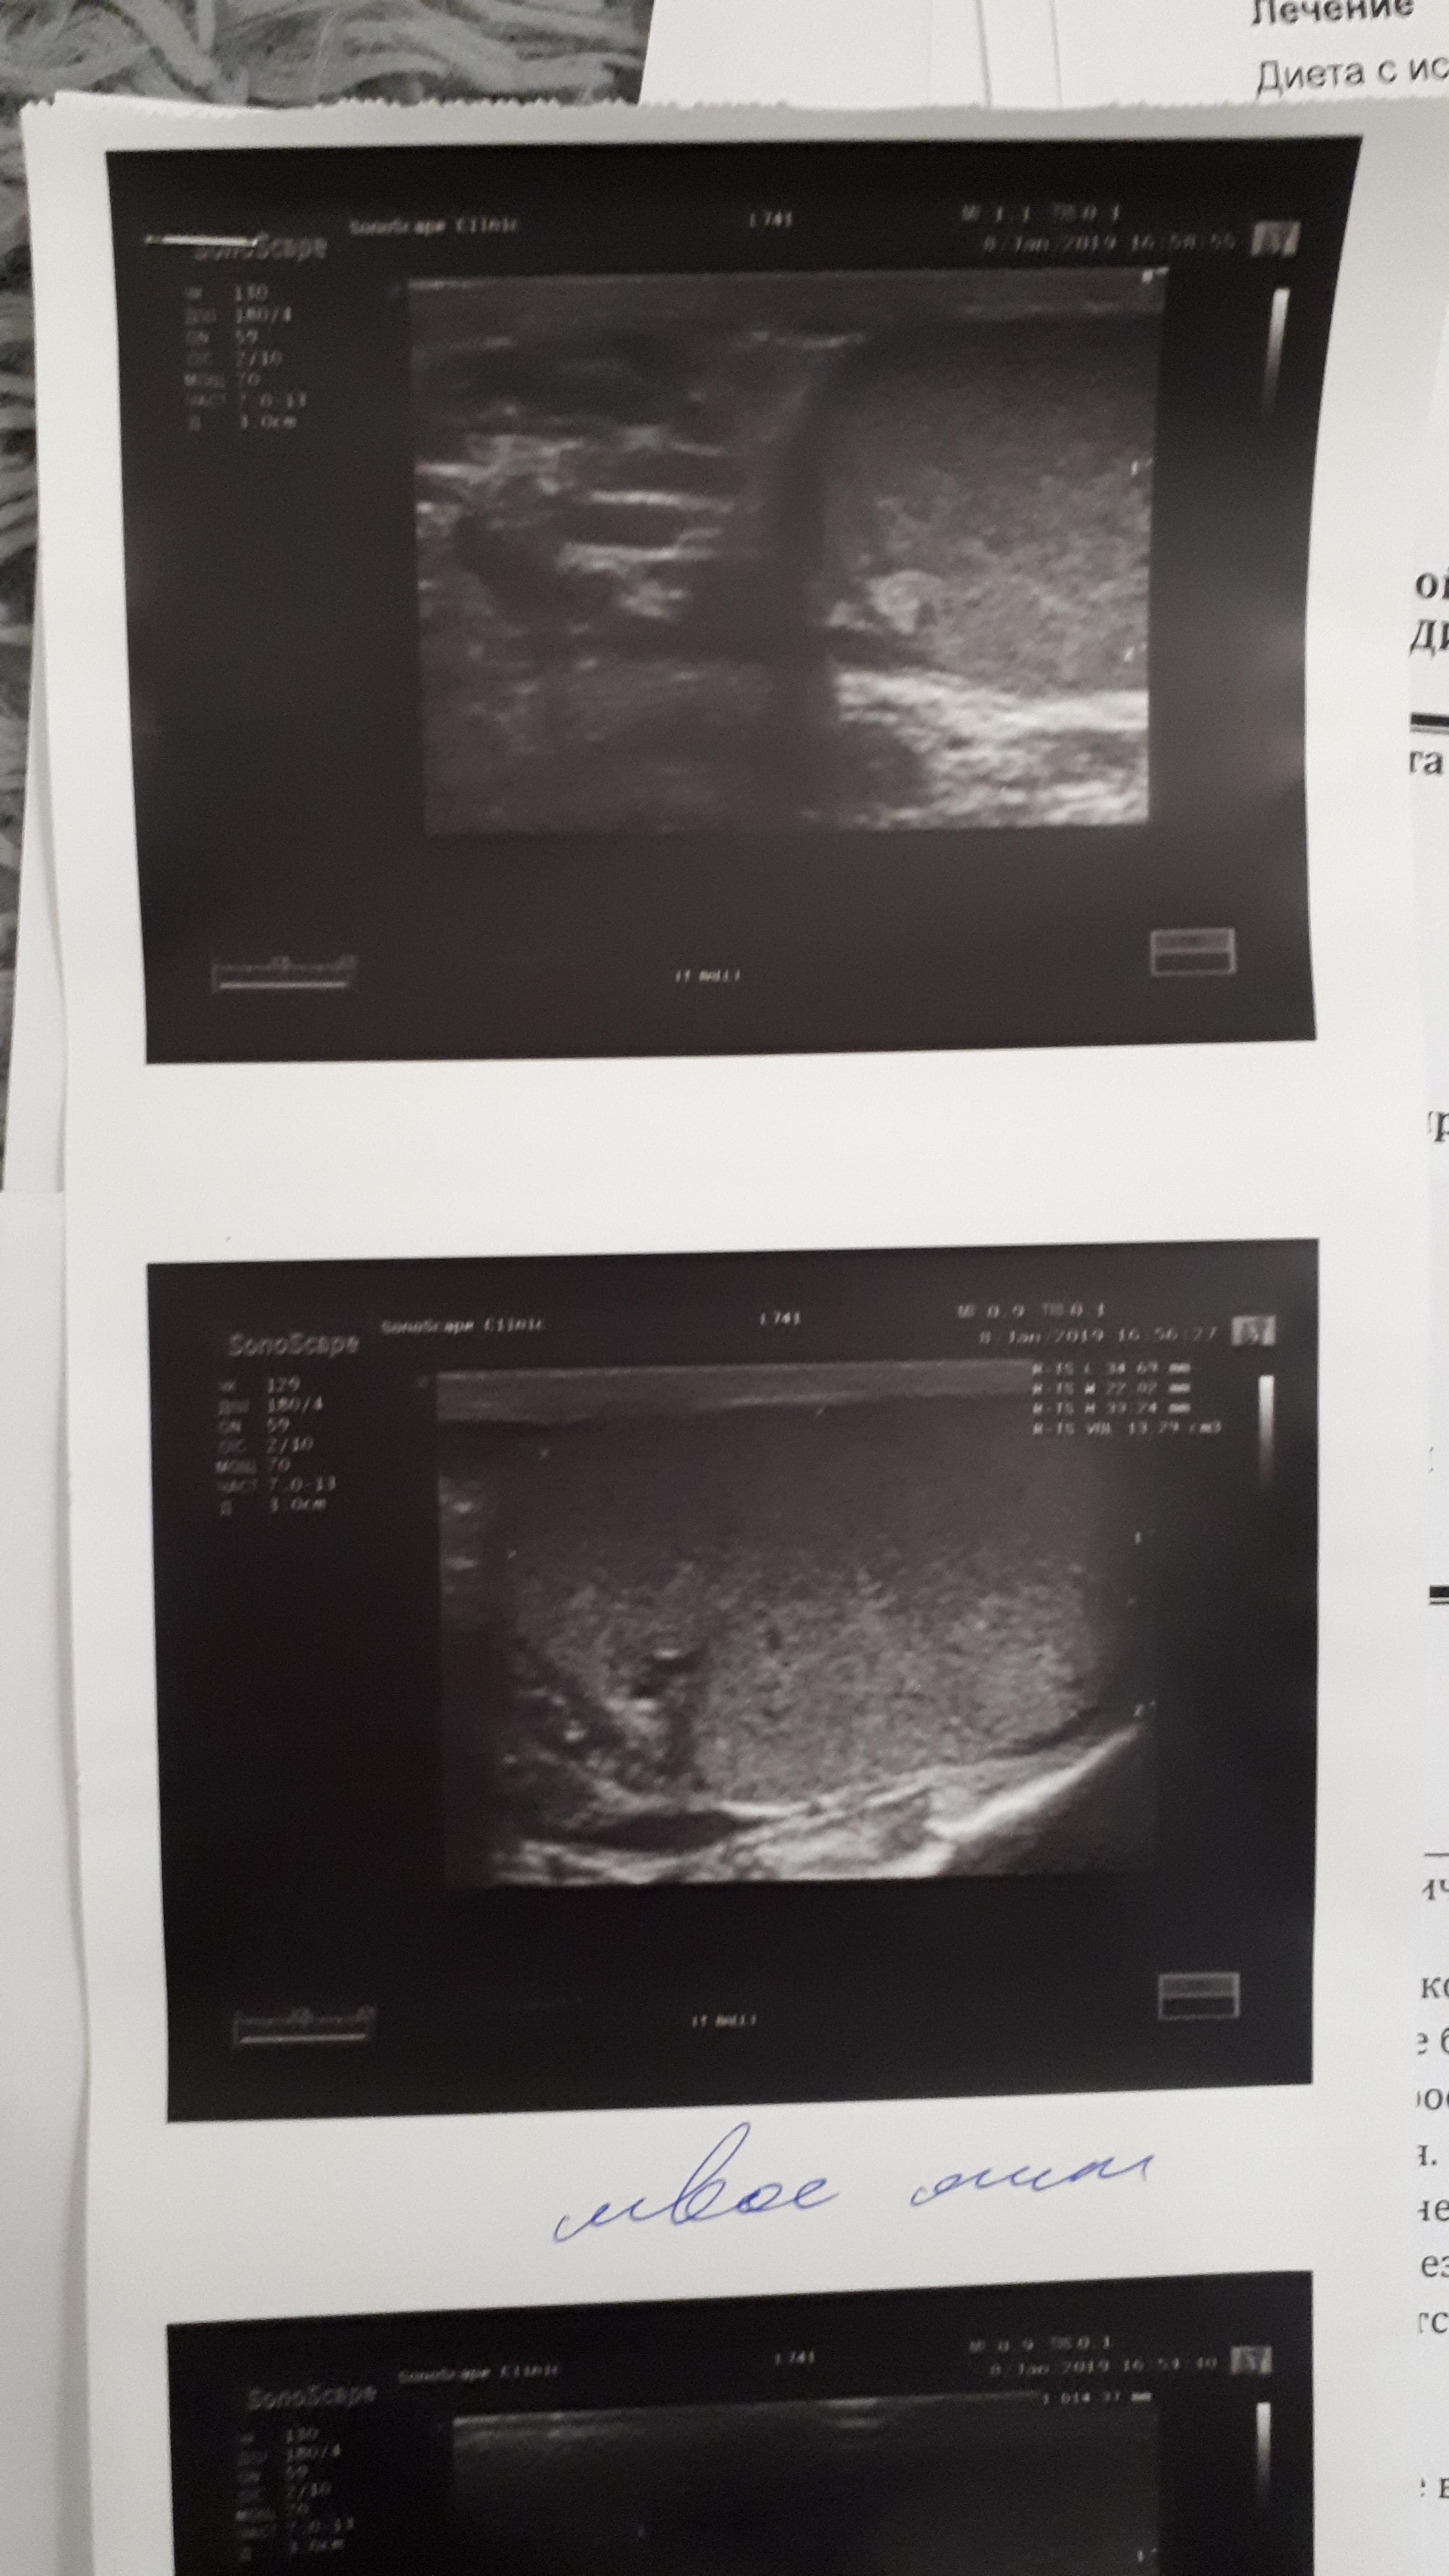

здравствуйте, периодически беспокоят боли в правом яичке, обращался к трём урологам, сдавал на разные инфекции , ничего нет, по УЗИ поставили диагноз хр. эпидидимит, после назначенного не заметил сильного улучшения, боли возвращаются, последний врач к которому обратился сказал будут боли , свечи вольтарен и все. Есть ли лечение при обострении этой болезни? Как мне самому кажется первые боли появились после не сильного удара по правому яичку.